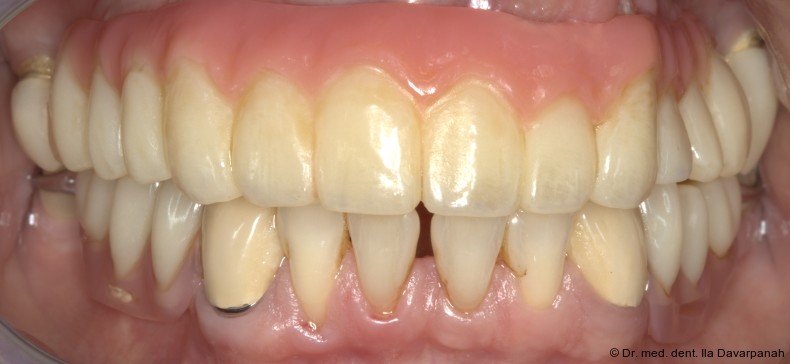

Die definitive Prothese konnte im dritten Behandlungstermin problemlos eingegliedert werden. Es waren lediglich minimale okklusale Anpassungen erforderlich (Abb. 20–24).